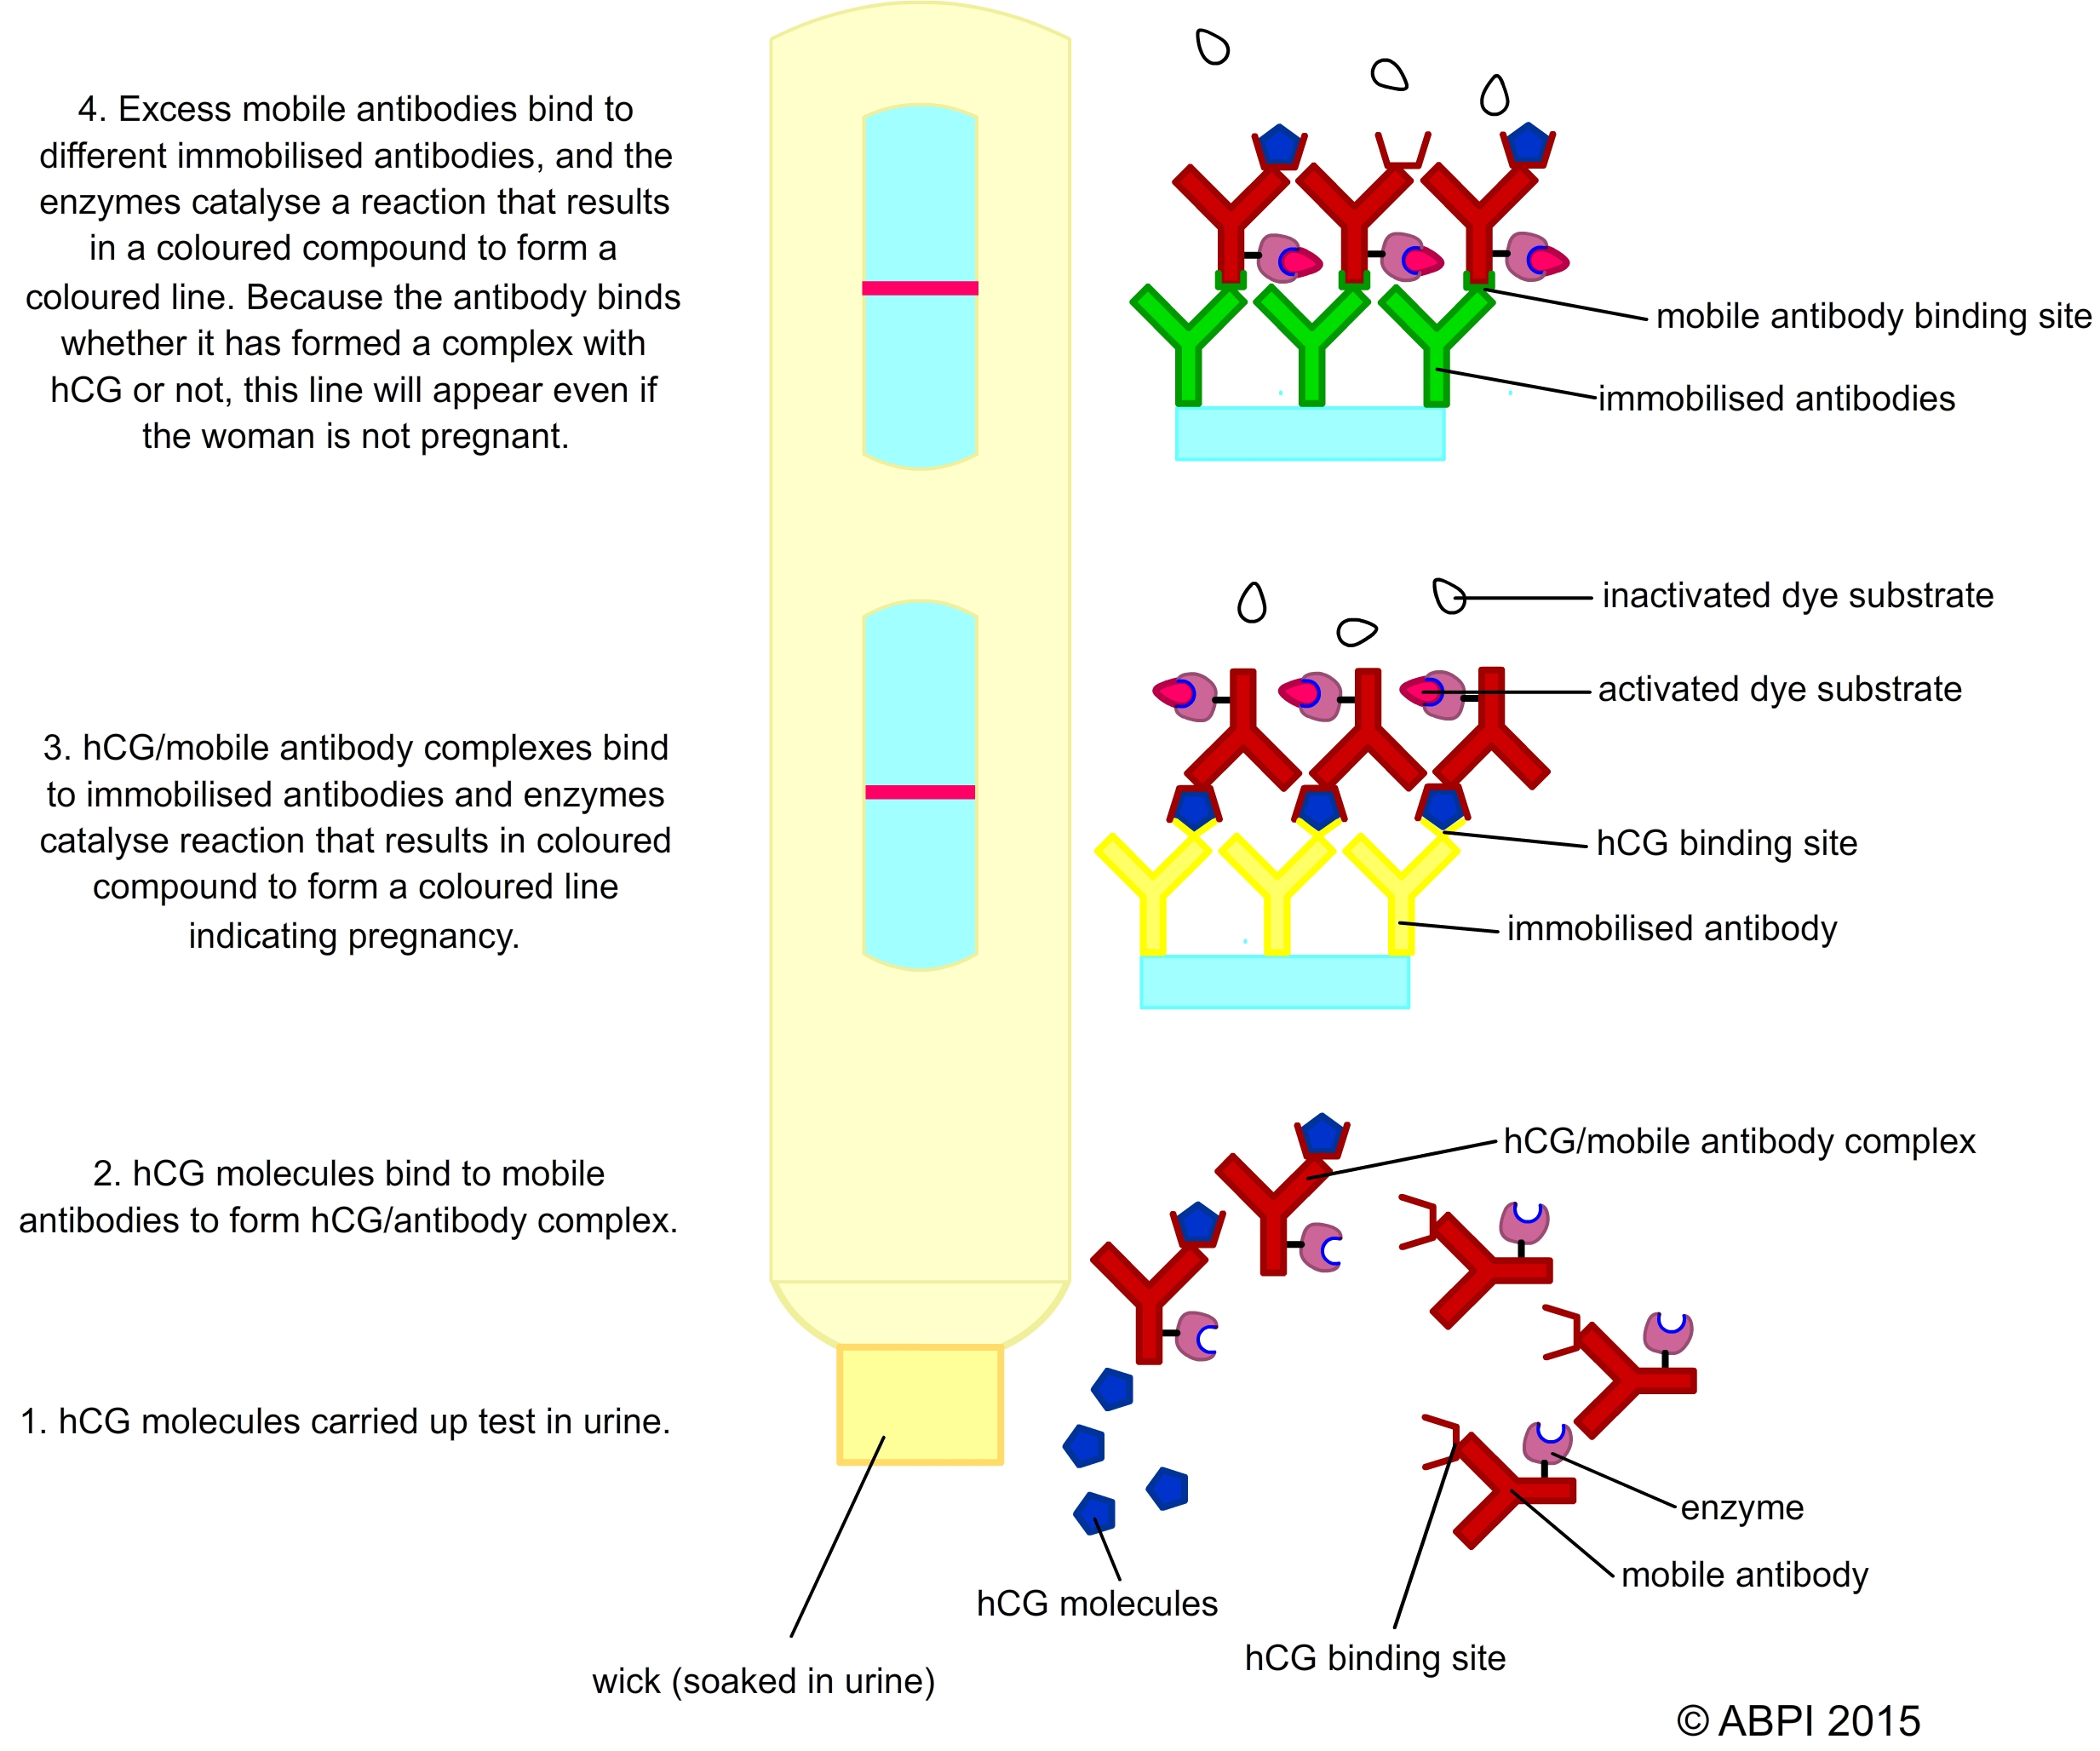

Example: ELISA used in pregnancy testing

As a human embryo begins to implant in the uterus and develop it produces a chemical called Human Chorionic Gonadotrophin (hCG). Some of this hormone is found in the blood and the urine of the mother. Modern pregnancy tests rely on monoclonal antibodies to test for hGC in the urine. Some pregnancy tests are so sensitive that pregnancy can be detected within hours of implantation. Often a pregnancy test is carried out first thing in the morning, when the levels of hGC are highest. A pregnancy test contains mobile monoclonal antibodies for hGC that have enzymes attached to them. They will only bind to hCG. If the woman is pregnant the hCG in her urine binds to the mobile monoclonal antibodies and forms an hCG/antibody complex (complete with enzymes). These complexes bind to immobilised antibodies arranged in a line or a pattern such as a positive (+) sign when the enzymes catalyse a reaction to produce a coloured mark. If the woman is pregnant, a coloured line or pattern appears in the first window.

The urine then continues up through the test to a second window. Here there is usually a line of immobilised monoclonal antibodies that bind only to the mobile antibodies, regardless of whether they are bound to hCG or not. Again when the mobile antibodies bind it triggers an enzyme reaction that results in a coloured line. This coloured line forms regardless of whether the woman is pregnant – it simply indicates that the test is working.

If the woman is pregnant, two coloured patterns appear. If she is not pregnant, only one appears.

Using enzymes to help diagnose pregnancy – it is the action of enzymes that causes the formation of the coloured lines that indicate pregnancy